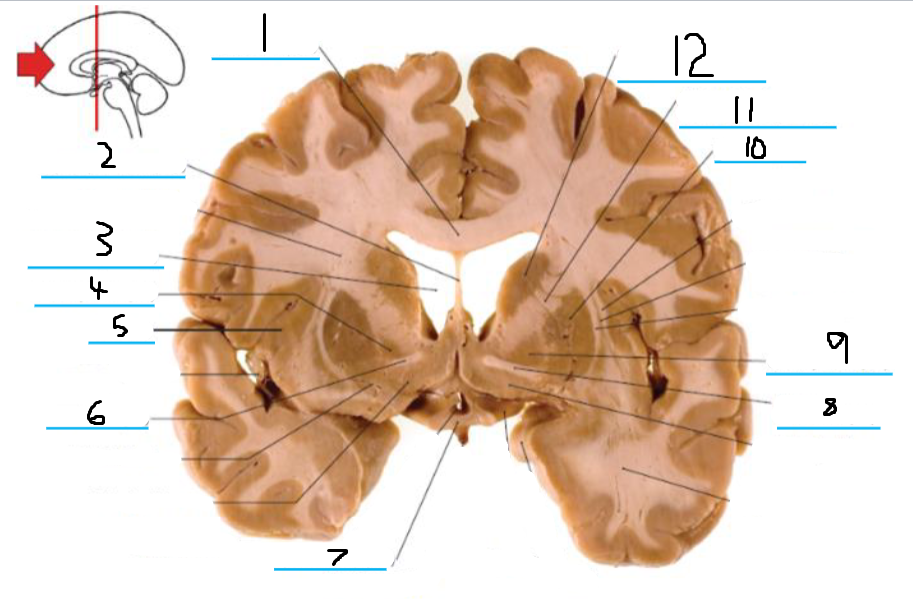

#1 is the:

Cingulate Gyrus

#2 is the:

Septum Pellucidum

#3 is the:

Lateral Ventricle

#4, #7, and #12 is the:

Fornix

#5 is the:

Third Ventricle

#6 is the:

Anterior Commissure

#8 and #11 is the:

Amygdala

#9 is the:

Hypothalamus

#10 is the:

Mammillary Body

#13 is the:

Insula

#14 is the:

Globus Pallidus

#15 is the:

Putamen

#16 is the:

Internal Capsule

#17 is the:

Caudate

#18 is the:

Corpus Callosum